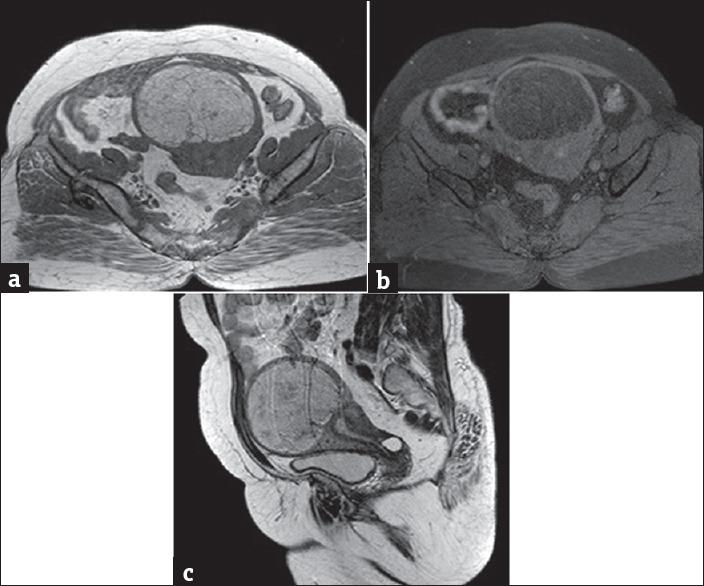

We report two cases of uterine lipoleiomyoma in postmenopausal women of ages 52 and 55 years, who presented with complaints of leukorrhea and lower abdominal pain, respectively. Lipoleiomyoma is a rare benign variant of leiomyoma, having an incidence of 0.03%-0.2%. These are benign pelvic tumors which are usually asymptomatic and commonly occur in obese postmenopausal women. However, they can occasionally present with typical leiomyoma symptoms. Imaging plays a crucial role in the diagnosis of benign pelvic tumors. Ultrasonography is the first imaging modality for diagnosis of pelvic tumors in females. Computed tomography and magnetic resonance imaging are specific in demonstrating the uterine origin and fat component.